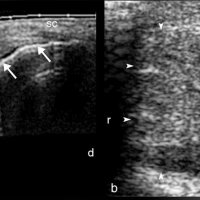

Ultrasound reveals increased AP thickness of the tendon >7 mm in males and >6 mm in females, also loss of normal tendon appearance with multiple hypoechoic foci within the tendon.